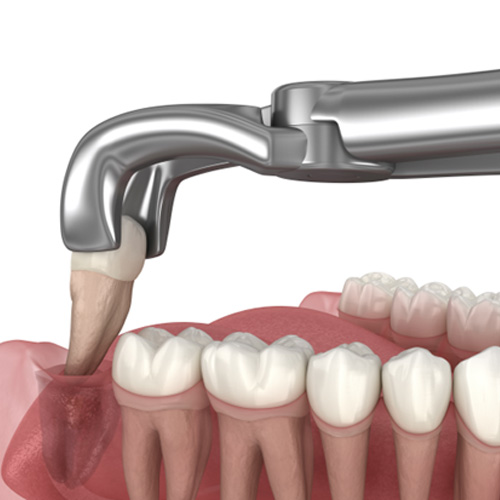

The procedure will be completed with our experienced and caring oral surgeon, Dr. Mohamed Ali Boukheir. If the wisdom teeth that need to be extracted have already broken through the gumline, then he will rock them loose, remove them from the socket, and tend to the extraction site. If they are still trapped underneath the gumline, then he will need to make a small incision in your gums first to access them. Then, he can remove each tooth section by section.